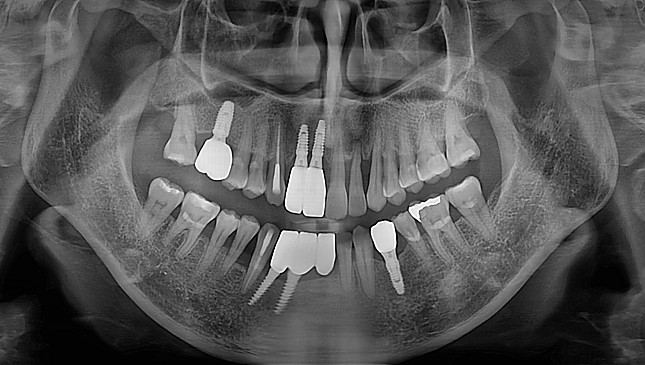

치아살리기 치료 전후 사진

잇몸재생교정 치료 전후사진

잇몸 전체가 무너져 동시다발적으로 죽어가던 치아들을 한꺼번에 살려 냅니다.